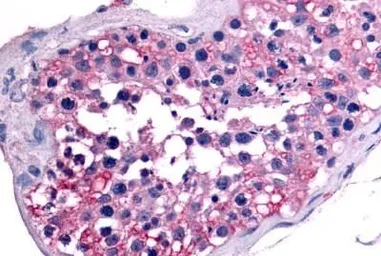

ApplicationsIHC-P